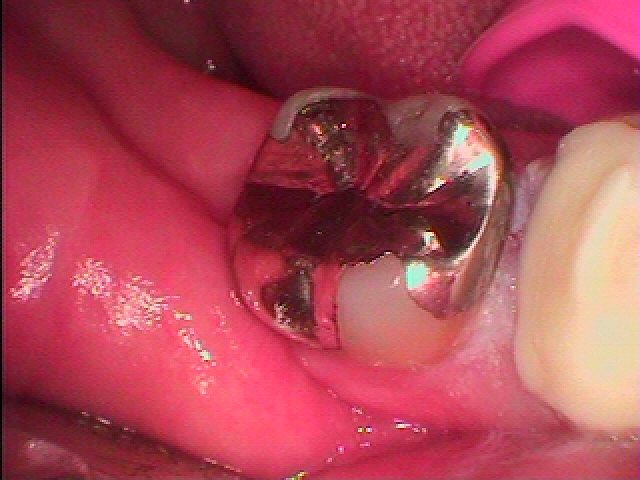

しっかり治療してないと銀歯の下は悪くなっていきます。| |広島市安佐南区の歯科医院 しっかり治療してないと銀歯の下は悪くなっていきます。 トップ お知らせ・ブログ しっかり治療してないと銀歯の下は悪くなっていきます。 しっかり治療してないと銀歯の下は悪くなっていきます。 Web診療予約 初めての方へ 選ばれ続ける理由 院内設備について 歯が痛いしみる一般歯科 歯がぐらぐらする歯周病 健康な歯を保ちたい予防歯科 子供の虫歯予防をしたい小児歯科 銀歯をセラミックに審美歯科 白い歯を目指しませんか?ホワイトニング 矯正専門医がいるので安心矯正歯科 抜けた歯を補いたいインプラント・入れ歯 医院案内 スタッフ紹介 メリィハウス歯科クリニックオフィシャルホームページ ラベンダー歯科クリニックオフィシャルホームページ お知らせ・ブログ ホーム 診療科目 一般歯科 歯周病治療 予防治療 小児歯科 審美治療 ホワイトニング 矯正歯科 入れ歯・インプラント マウスピース矯正 初めての方へ 院長・スタッフ 設備紹介 医院案内・アクセス メニューを閉じる